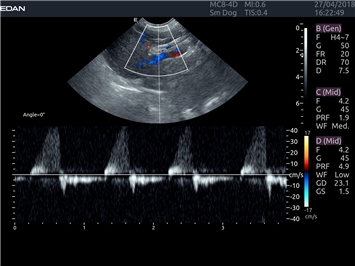

Постоянно-волновой допплер:

Да

Триплексное сканирование: